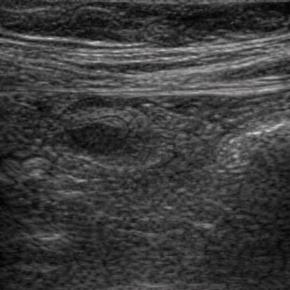

Elastography for the differential diagnosis of malignant versus benign testicular lesions: a meta-analysis

Ziwei Lin, Rui Lin, Huaiyu Wu, Linghu Wu, Jieying Zeng, Jinfeng Xu, Fajin Dong